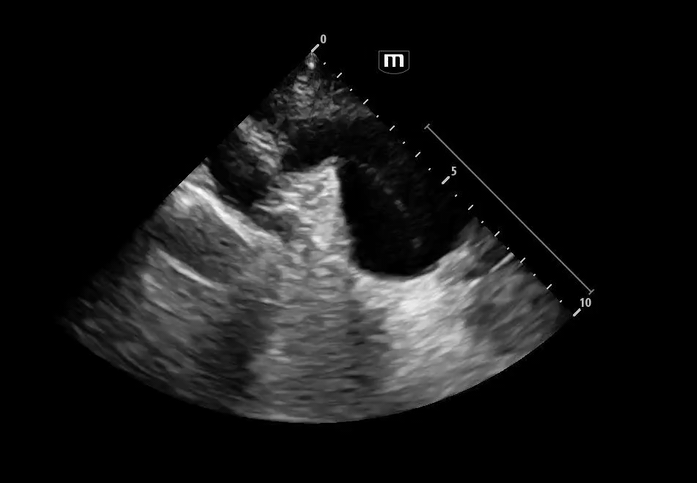

Image 3 - 5: Suprasternal notch

Interpretation: Dilated aortic arch including both ascending and descending aorta with linear echogenic structure within the lumen consistent with an intimal flap, as well as appearance of true and false lumens within the arch.

Ultrasound Findings in Aortic Dissection

• Intimal flap within the lumen

• Double lumen appearance

• Ascending aortic dilation

• Aortic arch involvement on suprasternal view